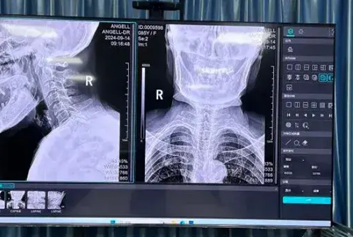

在医院的诊疗流程中,有这样一个隐形环节:它不直接与患者对话,却贯穿影像检查的全流程;它没有显眼的诊疗仪器,却能决定影像报告的精准度;它就是医学影像质控。从一张CT片的清晰度,到一份MRI报告的规范性,再到病灶诊断的准确性,背后都离不开影像质控的默默守护。让我们跟着云胶片/超声工作站迈德卫云PACS一...